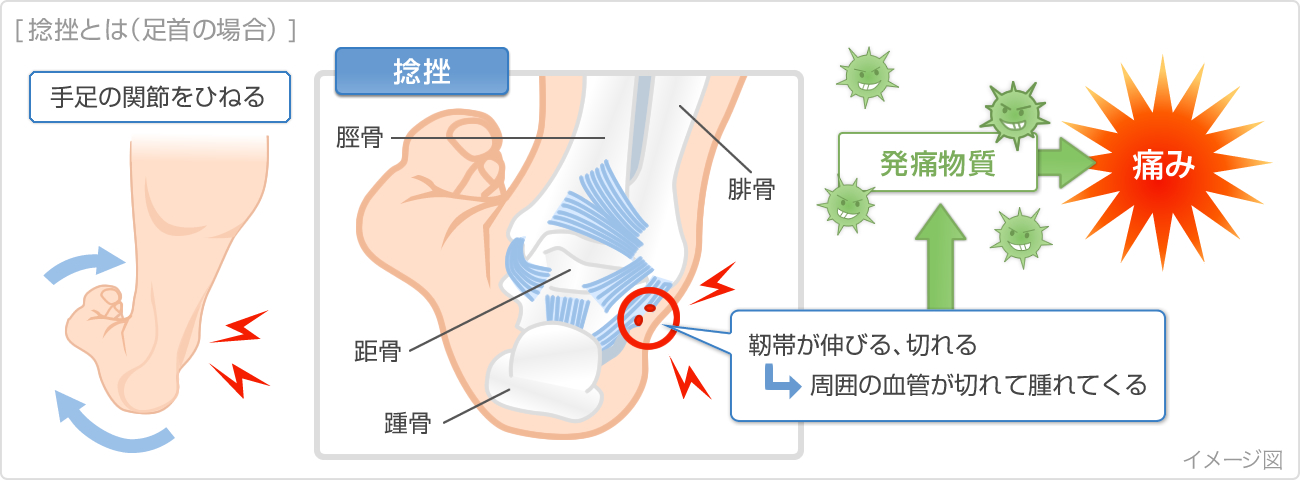

捻挫(ねんざ)したらどうする? 捻挫(ねんざ)は、とくに足首や指に起こりやすく、関節をひねって痛めてしまうことで起こります。 靭帯の損傷などが考えれらる場合は、整形外科での治療が必要です。 目立った腫れやひどい痛みといった症状がなければセルフケアで様子をみてもよいでしょう。 捻挫(ねんざ)直後の応急処置や、その後の手当についても · 特に応急処置の際、捻挫の患部に温湿布を貼ることは禁物です。 軽度の捻挫でも、しばらくは飲酒、湯船に浸かる入浴、運動などは避けましょう。 また、立ち仕事も数日は控え、医師の指示に従いながら再開するようにしましょう。2601 · 足首の外側が痛む場合は、 湿布を半分に折って中心部分に切れ込み をいれましょう。

捻挫で湿布を使用する期間はいつまで? 冷やす温めるが大切です! スポンサーリンク 捻挫というのは靭帯が損傷する怪我です。 靭帯を損傷すると痛みだけでなく、腫れや内出血を伴いこともあります。 きちんと処置することによって早期完治だけでなく再発を防ぐことや癖になることを防ぎます。 この場合に湿布を使用する期間というのはいつまででしょうか

捻挫 ねんざ の症状 原因 くすりと健康の情報局